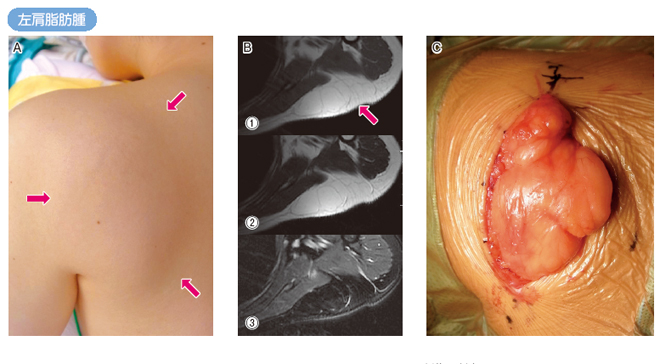

軟部腫瘍の画像診断に関する専門書。- タイトル: 軟部腫瘍の画像診断- 出版社: 秀潤社- タイトル: 画像診断- 巻号: 09- 巻号: Vol.37 No.10 2017ご覧いただきありがとうございます。